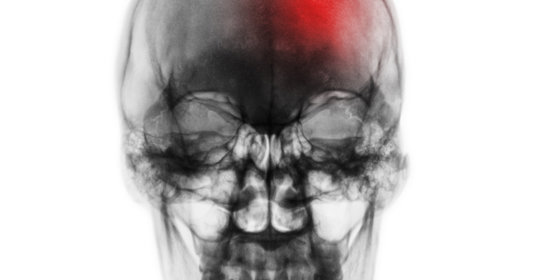

腦中風後遺症的症狀、前兆、治療和預防

腦震盪後遺症的症狀表現、前兆、治療與預防

腦溢血後遺症的症狀、前兆、治療和預防

腦血管破裂後遺症的症狀、前兆、治療和預防

腦梗塞後遺症的症狀、前兆、治療與預防

腦缺氧後遺症的症狀表現、前兆、治療及預防